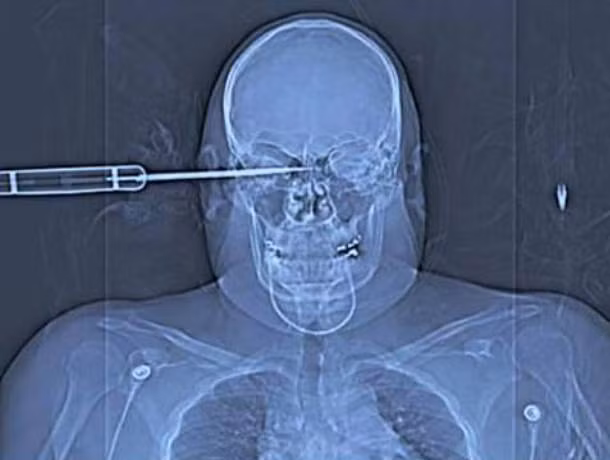

12. ...thêm một vụ "xuyên táo"...

Khi công nhân Ron Hunt ngã xuống từ một giàn giáo trong khi đang sử dụng một máy khoan cỡ lớn, mũi khoan đã... xuyên thẳng qua một hốc mắt của anh và để lại một phim X-quang cực kỳ rùng rợn như trên. Và, lại bằng một cách kỳ diệu nào đó, anh này đã tiêu hết vận may cả đời của mình để sống sót, hoàn toàn khỏe mạnh với một cái lỗ phía ót.